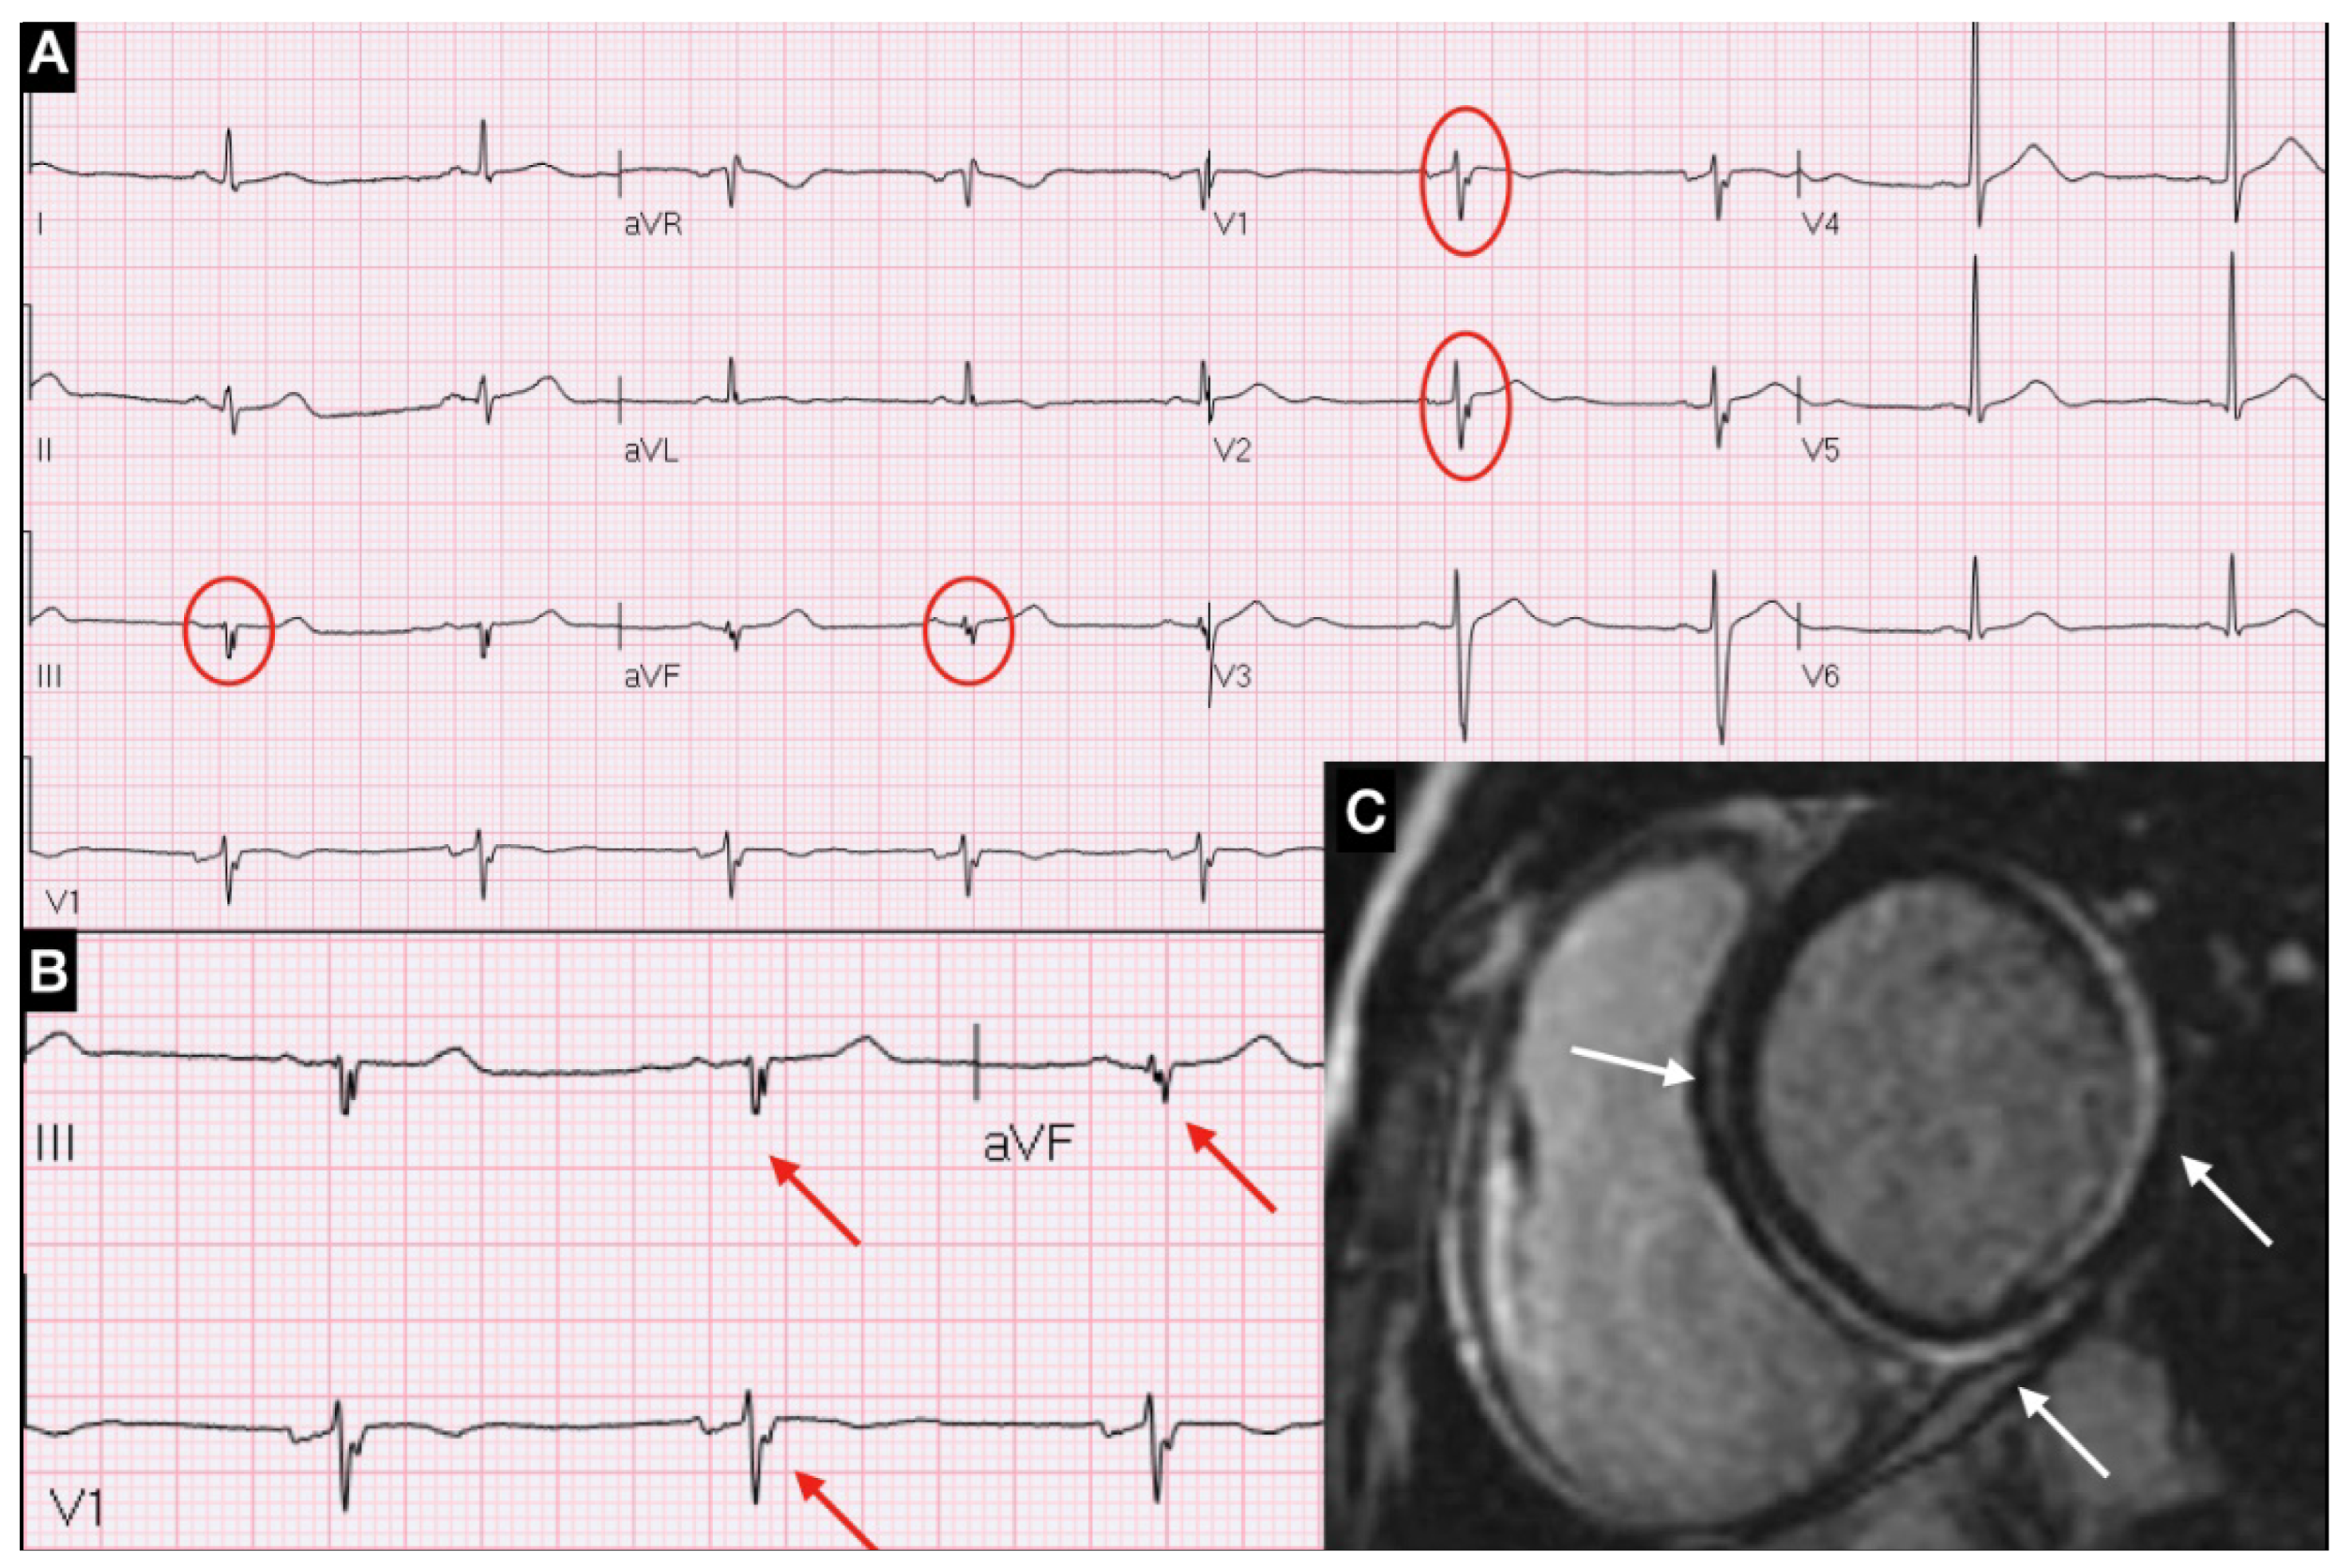

3.3. ECG and QRS Fragmentation

| QRS fragmentation, n (%) | 40 (78) |

| Latency of fQRS occurrence (days), median (IQR) | 3 (2–6) |

| fQRS matching LGE distribution, n (%) | 38 (95) |